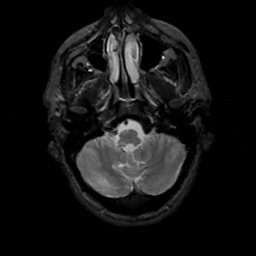

MR Study #6, March 17, 1991 -- Slice #8

[Home][Help][Clinical][Tour 1][Tour 2] Slice 8